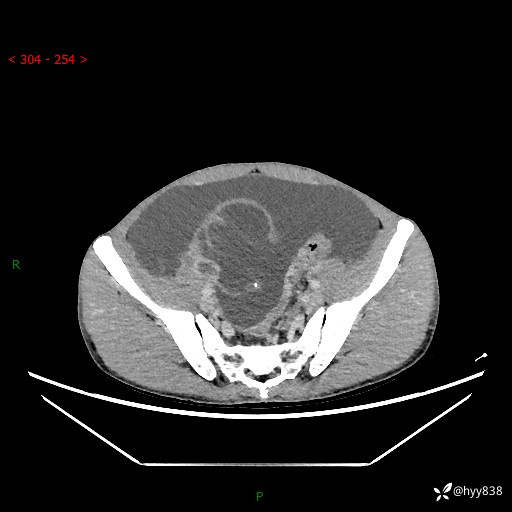

现病史:患者10天前无明显诱因出现腹部胀痛不适,无畏寒发热,无胸痛胸闷,无心慌气短,无恶心呕吐,无腹泻及黑便,无粘液血便及里急后重等症状,4天前在当地县人民医院就诊,行腹部CT示:下腹部占位性病变,腹腔及盆腔积液;今患者为求进一步诊治来我院治疗,门诊以“腹水”收治入院。 发病以来,精神饮食可,大小便正常,体重体力无明显变化。

腹部CT平扫+增强